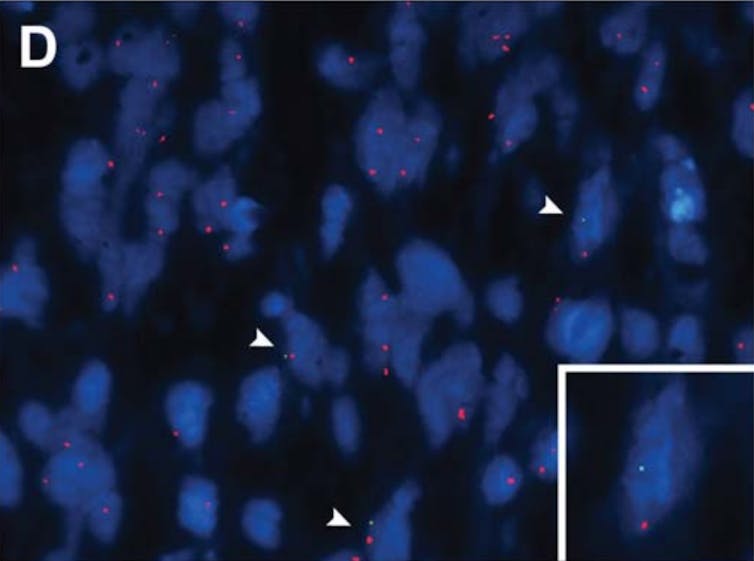

Hace relativamente poco, un estudio (el primero en la historia) revelaba la presencia de microquimerismo en el cerebro humano: se ha encontrado ADN con el cromosoma sexual Y (de varón) en múltiples lugares del cerebro de 37 mujeres ya fallecidas (de 59 mujeres totales).

El hallazgo es revolucionario. No se trataba de células pasivas, sino que estaban activas antes de morir, integradas funcionalmente en el tejido cerebral.

Para llegar allí, las células traspasan la placenta durante el embarazo y terminan atravesando la barrera hematoencefálica, una estructura altamente selectiva que regula el paso de sustancias entre la sangre y el cerebro. Superar uno de los sistemas de defensa más estrictos del organismo añade aún más misterio al descubrimiento.